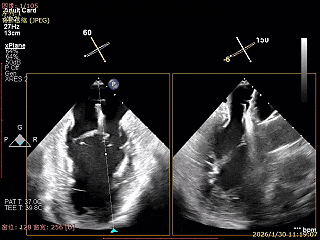

送入第2枚XTR在左房调整轨迹及Orientation

进入瓣下重新确认Orientation及位置

捕捞瓣叶,确定瓣叶瓣尖稳定插入夹臂后,Gripper Down

关紧后,前后叶受限明显

3D Enface下组织桥稳定无反流

夹子释放后,反流基本消失

LVOT切面可见主瓣二尖瓣术后反流基本消失

植入两枚夹子后二尖瓣平均跨瓣压差2mmHg